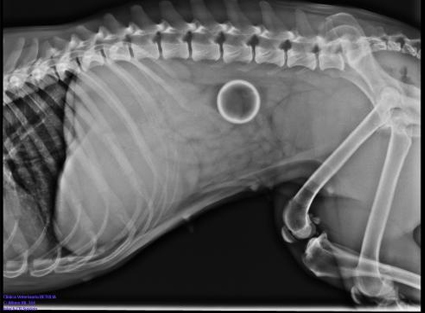

Radiología Torácica

- Evaluación de enfermedades pulmonares

- Diagnóstico de infecciones respiratorias

- Identificación de masas o tumores

- Evaluación cardíaca básica

Radiología Digestiva

- Estudios con contraste (esófago, estómago, intestinos)

- Detección de cuerpos extraños

- Evaluación de obstrucciones intestinales